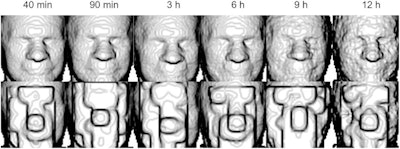

In response to these "identifiability concerns," the researchers aimed to validate a method that to thwart these steps. They conducted a study that included 30 healthy volunteers who underwent total-body F-18 FDG-PET/CT scans (uEXPLORER, United Imaging) at multiple time points during a single visit. Next, they used available surface rendering software on the reconstructed PET images to create separate images of each patient's face.

In a run on the sample, FaceNet correctly matched the faces rendered from the PET images to the PET images themselves at a maximum rate of 64%. The researchers then obscured the PET images using a pixilation process ("de-facing") they developed and found that this rate dropped to 7%.

"The proposed workflow reliably detected and obscured faces in both CT and F-18 FDG-PET images," the group wrote.